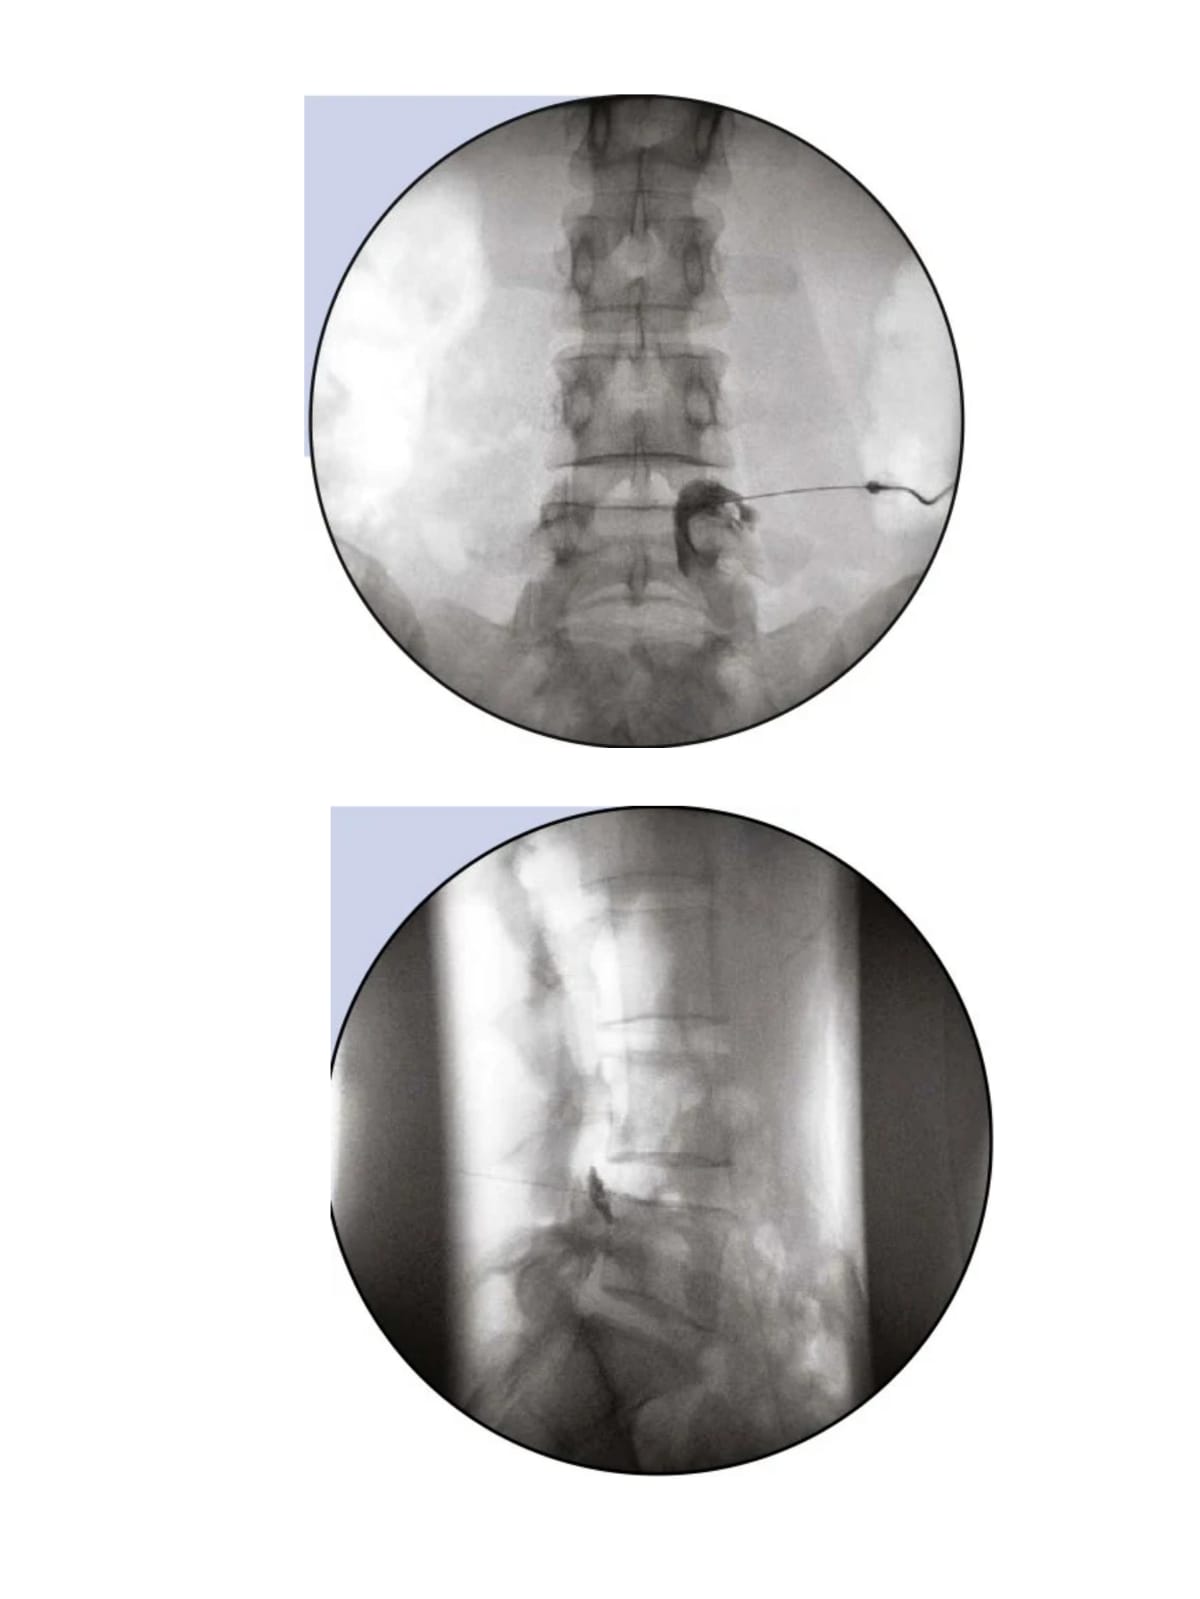

About Imaging Guided Procedures

This involves the use of imaging to target painful structures for injection of regenerative therapy (Biologics) and identify nerves carrying painful sensation and target them to achieve pain relief.

Different types of imaging used in pain practise are fluoroscopic guidance and Ultrasound guidance.

The procedure is done in operation theatre under local anesthesia.

All of these procedures take less than 1 hour. After the procedure is over the patient is shifted to recovery room and monitored for any postoperative complications/ drug reactions for 2 hours.

There are minimal side effects when the procedure is performed after adequate preparation and under imaging guidance by skilled hands.